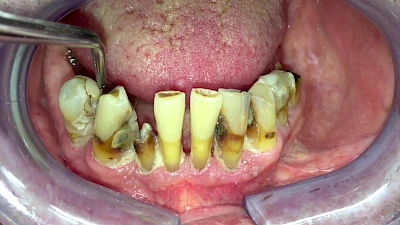

Eine geringe spürbare Beweglichkeit der Zähne ist durchaus normal, da Zähne über Fasern im Kieferknochen aufgehängt sind. Lassen sich Zähne, Kronen oder Brücken jedoch deutlich sichtbar bewegen, besteht die Gefahr, dass sie sich lösen und verschluckt oder aspiriert werden. Deshalb sollte in diesen Fällen der Zahnarzt verständigt werden.